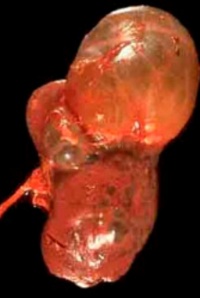

多囊肝绝大多数为先天性,即因先天发育的某些异常导致了肝囊肿的形成。多囊肝病人一般要到30-50岁时才出现症状,个别巨大囊肿的女性病人可以干扰分娩过程。囊肿逐渐缓慢地长大.病入主诉腹部膨隆,自已们到肿块。如果囊肿压迫邻近脏器,可出现相应症状。除非合并囊内出血、破裂或有囊肿蒂部扭转等合并症时可发生剧烈腹痛,一般疼痛不重。有时可有腹部胀满或重压感,食欲下降、恶心及呕吐。偶因胆管梗阻引起黄疸

体检时可发现肝脏肿大,质地从软到硬,可显结节状。如合并多囊肾,触诊时可以扪到。如有肾功能受损,临床可见高皿压、心衰脑血管意外。